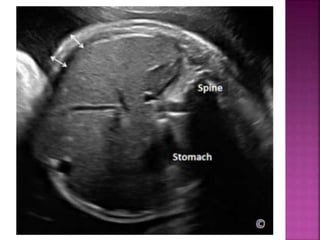

Fetal doppler & fetal growth